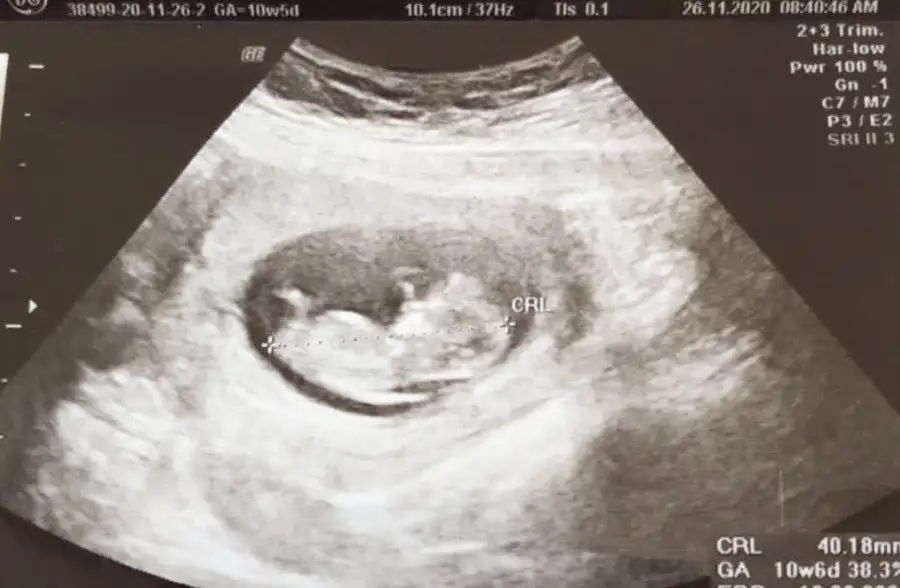

Şimdilik erkek yönünde nubu bunun için haftası küçük ilerleyen haftasında yükselirse nubu 12-13 haftasında teyit edeceğim erkekmi kizmi net belli olurÇoook tşk ederim anlamadım ama yani erkek yönünde derken bira anlıycağım sekilde söylermisiniz lütfenozamanda rıhatsız ederm çok saolun

Şimdilik erkek yönünde nubu bunun için haftası küçük ilerleyen haftasında yükselirse nubu 12-13 haftasında teyit edeceğim erkekmi kizmi net belli olur